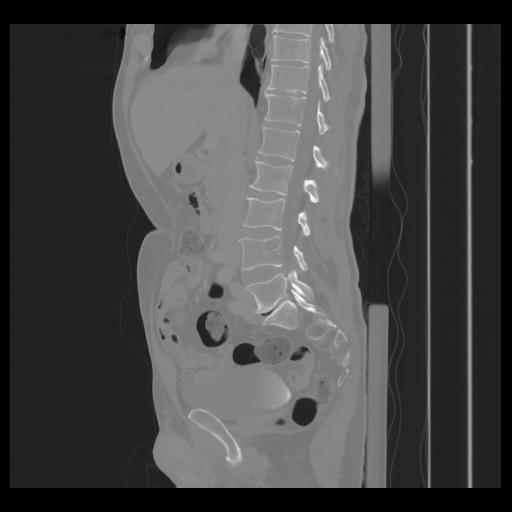

36 CUERPO,CE,Sagittal,3.000,CUERPO,Sagittal,